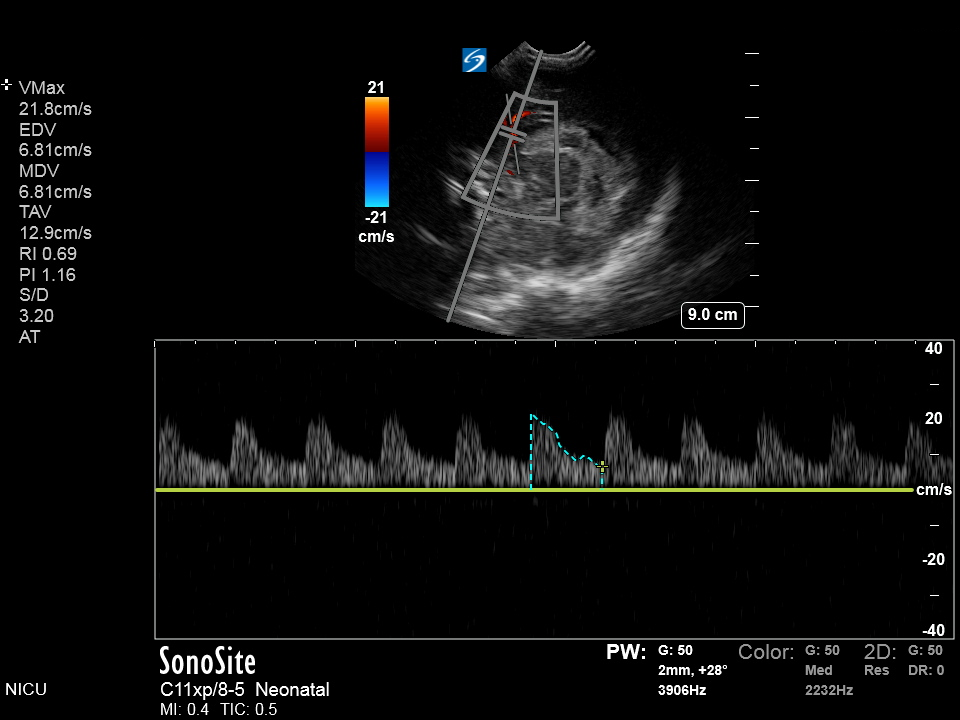

Neonatology IVH Graph Image